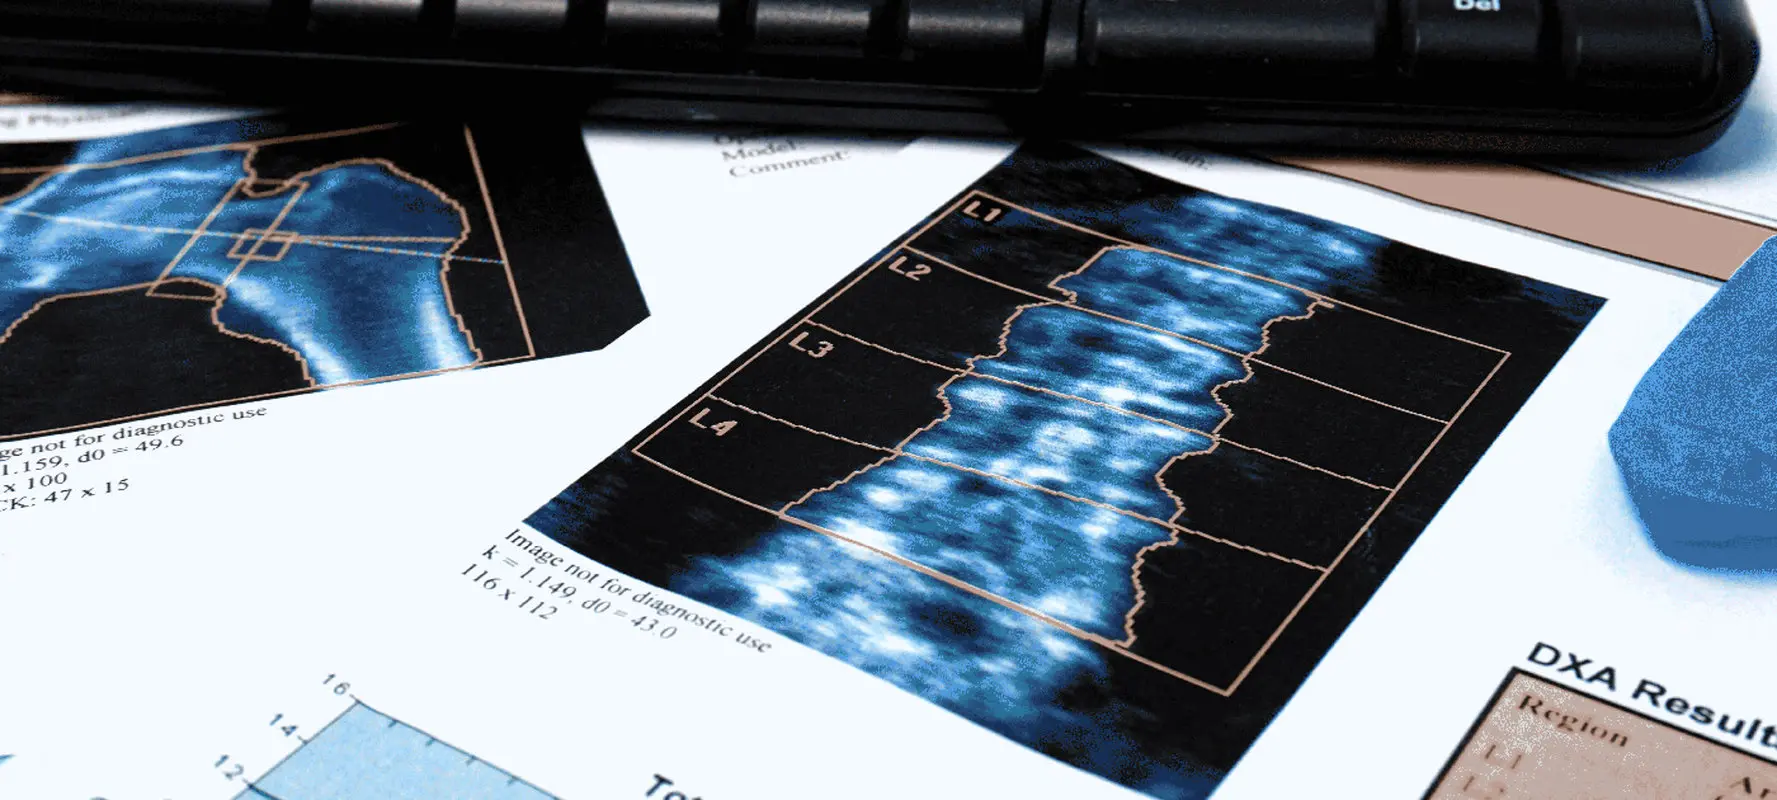

در این آزمایش از اشعه ایکس استفاده میشود تا کلسیم و سایر مواد معدنی استخوان در یک بخش از آن اندازهگیری شود. استخوانهای ستون فقرات، لگن و گاهی اوقات ساعد، استخوانهایی هستند که بیشتر مورد آزمایش قرار میگیرند.

نتایج تراکم استخوان که از طریق تکنیکهای تشخیصی مختلف مانند جذب سنجی اشعه ایکس با انرژی دوگانه (DEXA) و توموگرافی کامپیوتری کمی (QCT) به دست میآید، بینشهای ارزشمندی را درباره سلامت اسکلتی فرد ارائه میدهد. تفسیر این نتایج مستلزم درک اندازهگیریها و معنای آنهاست. به همین منظور در این بخش قصد داریم نگاه جامعتری به نتایج این سنجش و نحوه تفسیر آن بیندازیم.

تجزیه و تحلیل نتایج DEXA

نتایج DEXA معمولاً در گزارشی ارائه میشود که شامل امتیاز T برای مکانهای اسکلتی خاص مانند لگن و ستون فقرات است. تجزیه و تحلیل این نتایج مستلزم نگاه کردن به مقادیر عددی و طبقه بندی مربوط به آنها است. در طی این سنجش پزشکان ارزیابی میکنند که فرد در کدام محدوده طبیعی، استئوپنیک یا پوکی استخوان قرار میگیرد.